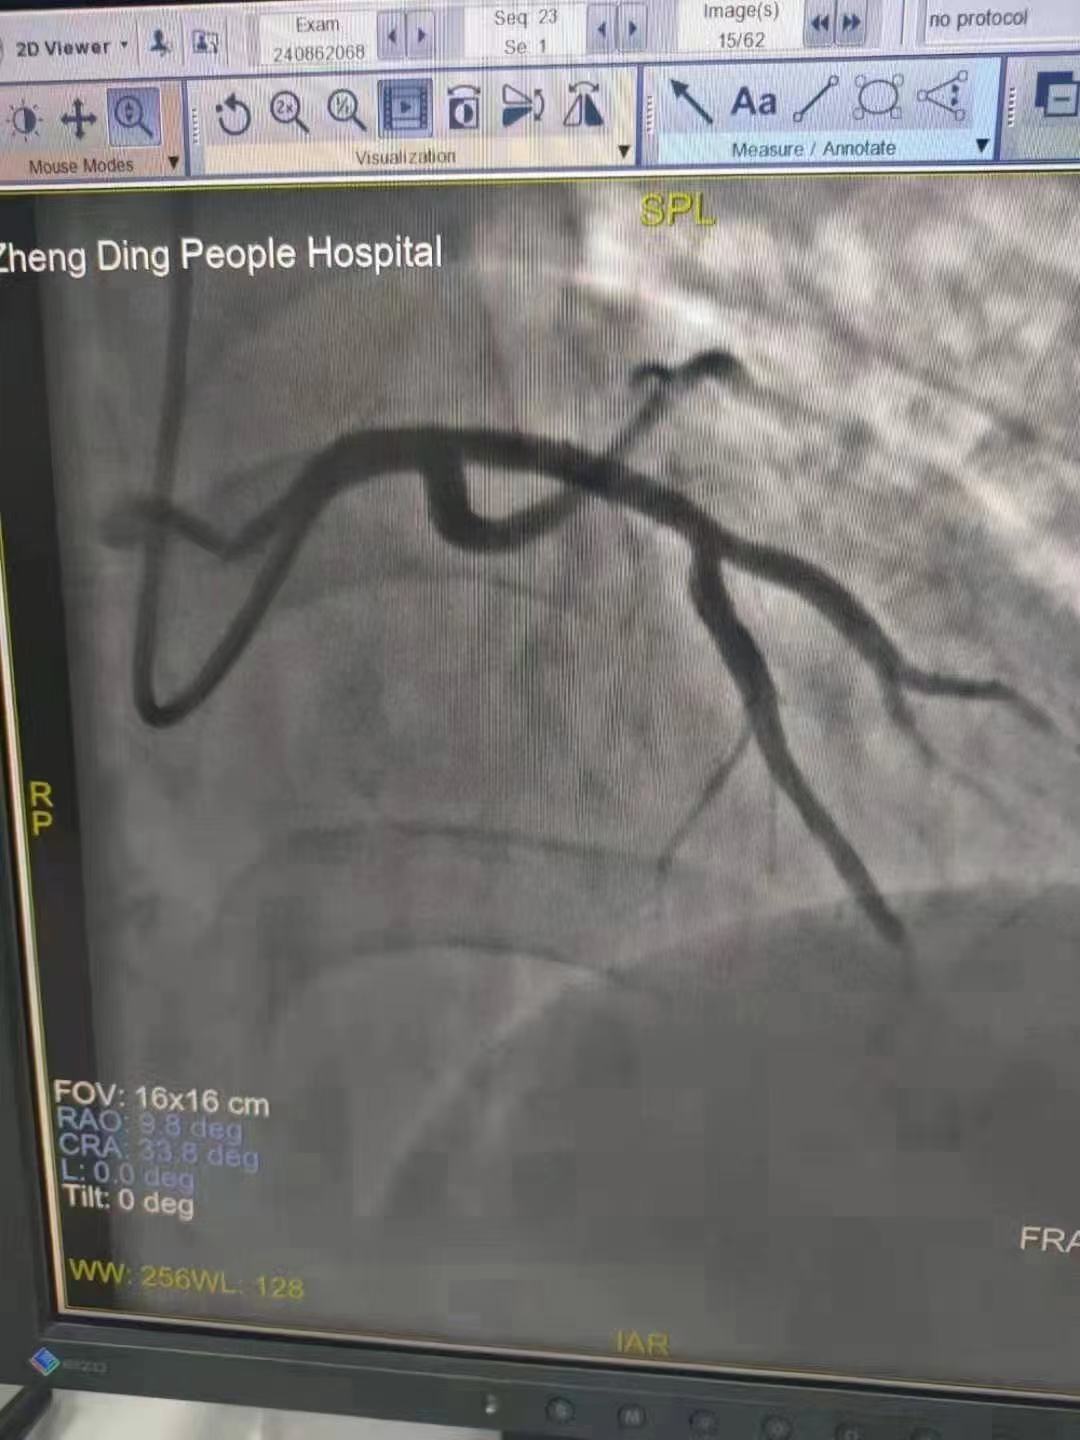

祝賀 正定縣醫院李京芳 主任團隊成功為患者植入Xinsorb生物可吸收支架!